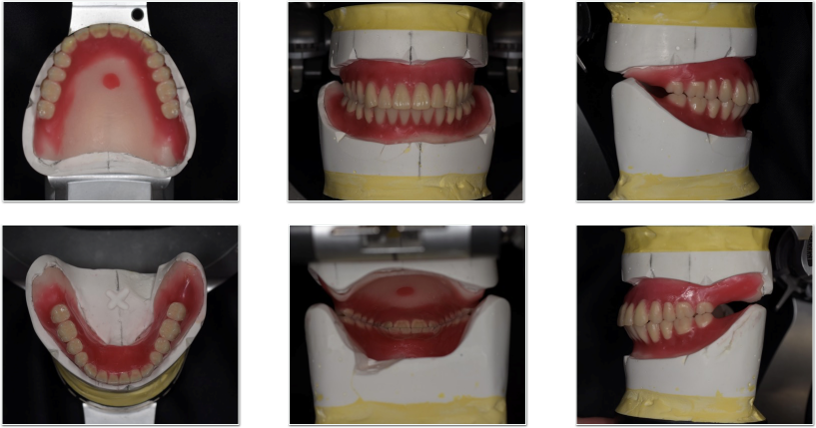

写真は、今までの入れ歯を全部持って来てくださった患者さまの入れ歯です。これだけ情報があると入れ歯治療のヒントが非常に得られます。

入れ歯(義歯)の写真

下顎にシリコンがしかれています。このシリコンに問題があるのでは?と目が行きがちですが、実際は入れ歯(義歯)の人工歯がかなり削れてしまっている事がわかりました。人工の歯が削れている為、噛んだ際に入れ歯(義歯)が安定しません。

この入れ歯の歯が、なぜこんなに削れてしまったのでしょうか?顎の位置がずれているのでしょうか?噛む位置がズレているのでしょうか?様々な問題が考えられます。

そのため、シリコンを入れ歯(義歯)の裏側に単につけたからといって、入れ歯(義歯)が痛くなく噛めるかといえば、そうは上手く行きません。

という事で、基本に戻って今の入れ歯の問題点を解決するべく、治療用義歯を作製して最後入れ歯(義歯)を作ることにしました。